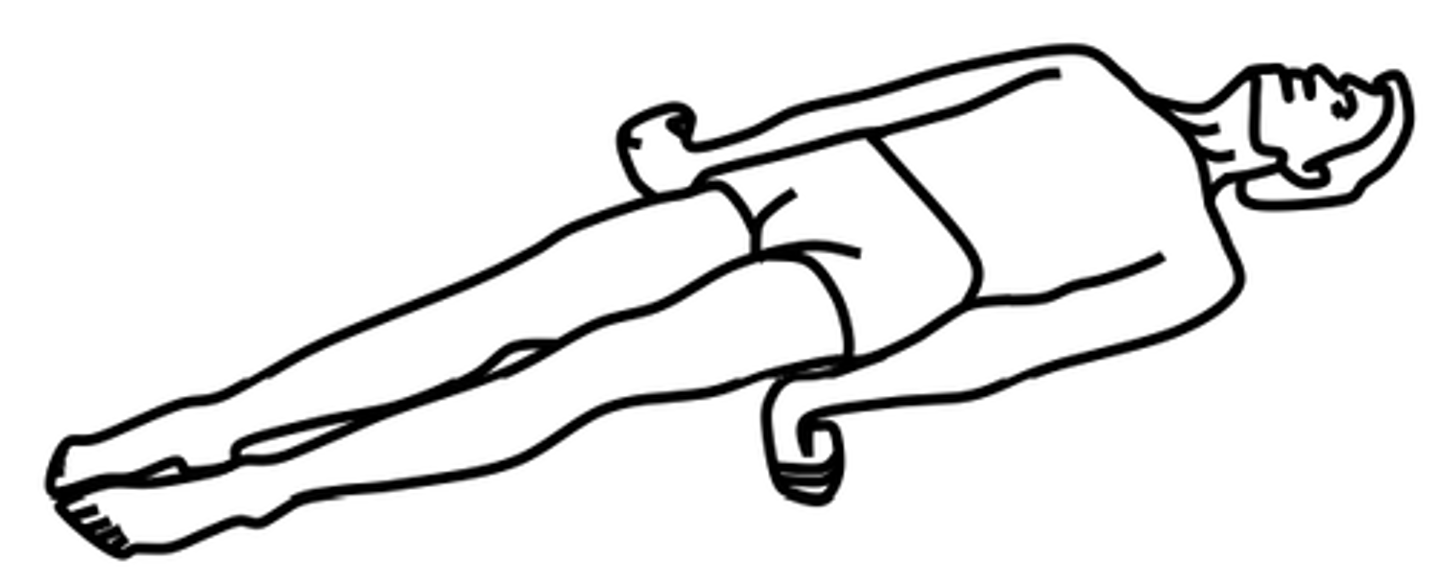

What is decerebrate posturing?

Abnormal body posture involves the arms and legs being extended straight out, the total is being pointed downward, and the head and neck being arched backwards.